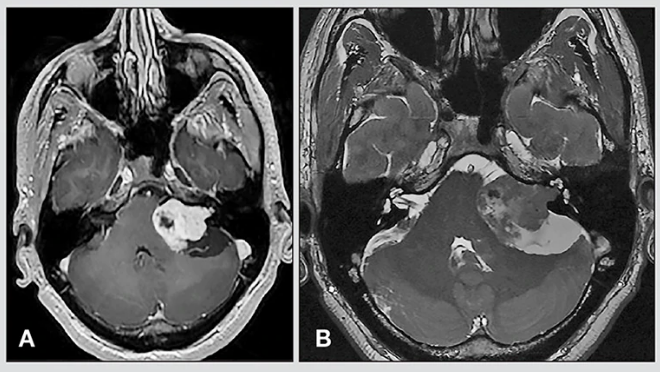

2、磁共振成像(MRI)扫描:利用强磁场中的无线电波而不是x射线拍摄内耳图像。MRI扫描通常能比CT扫描发现更小的听神经瘤。可以注射一种染料来进一步突出被检查的组织。